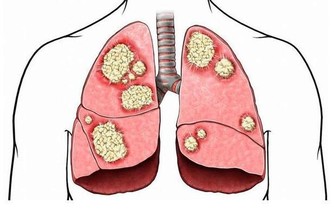

2、骨關節異常。一旦肺癌疾病發展到晚期,癌細胞分泌的特殊產物就會危及骨關節。肺癌細胞可產生某些特殊的內分泌激素(異源性激素)、抗原和酶,這些物質運轉作用於骨關節部位,而致骨關節腫脹疼痛,常累及脛、腓、尺、橈等骨及關節,指趾末端往往膨大呈杵狀指,x線攝片檢查可見骨膜增生。